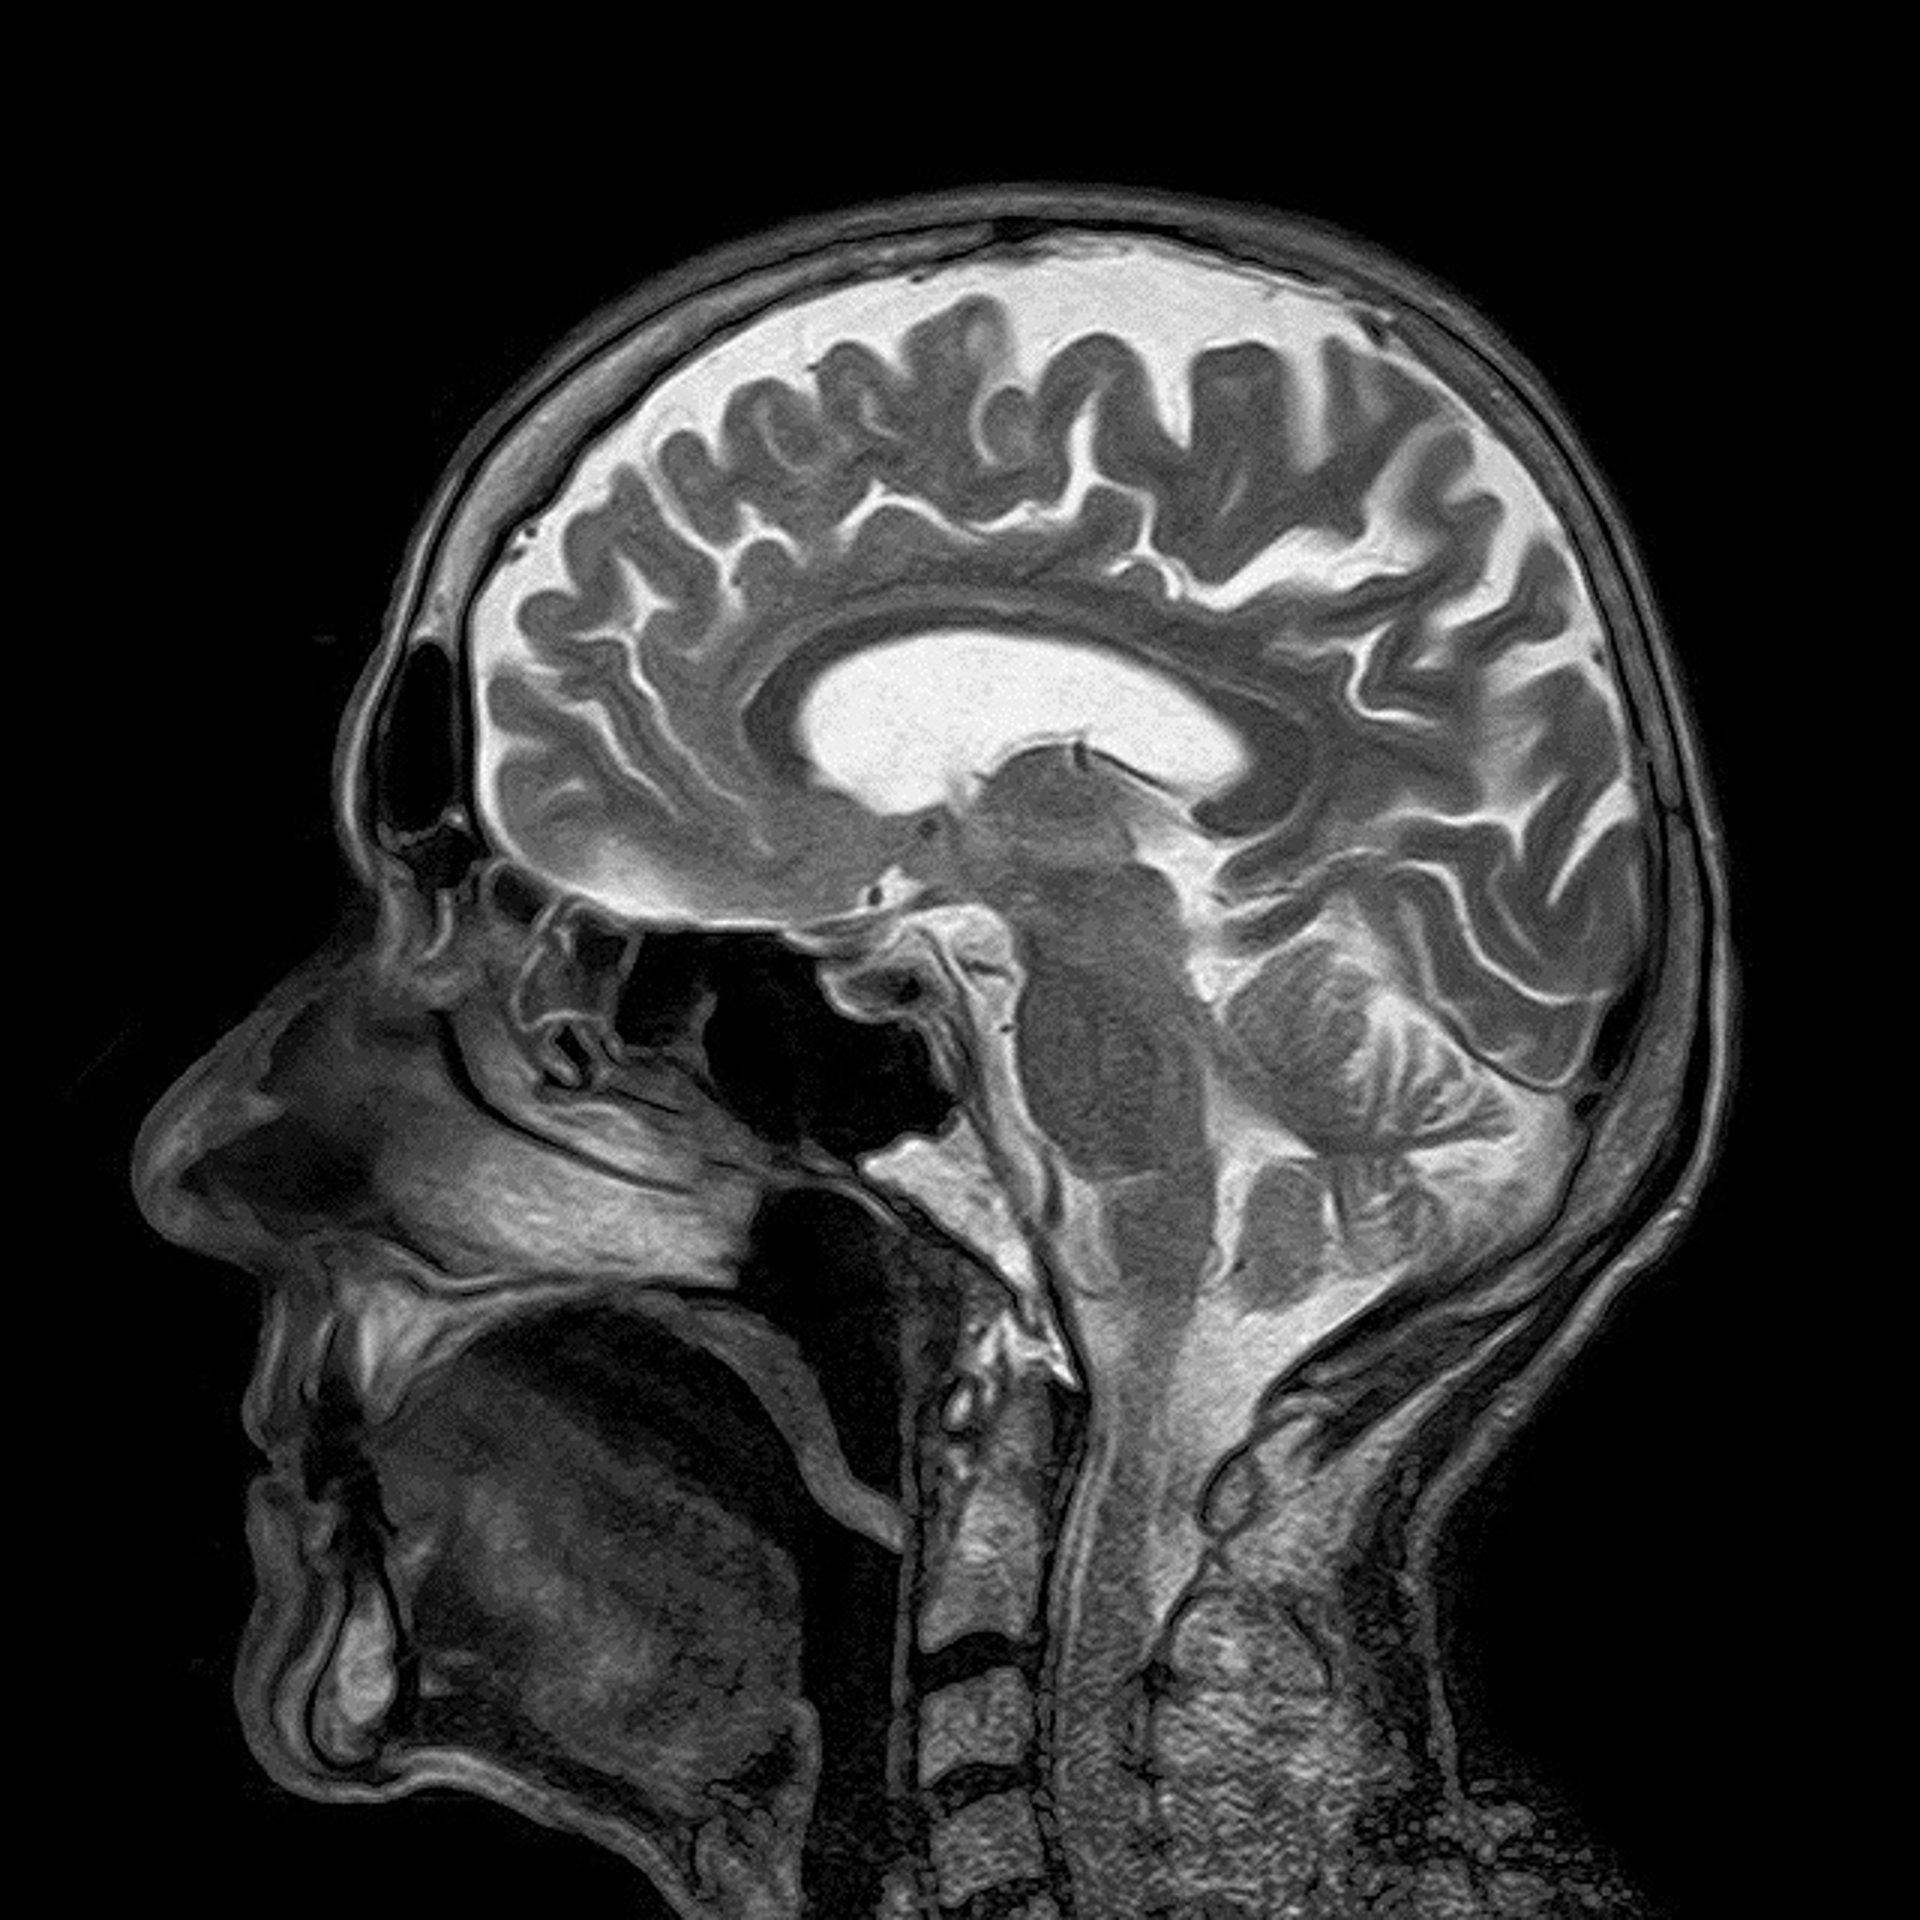

Investigadores del Instituto Científico San Raffaele de Milán (Italia) han conseguido identificar mediante un tipo de resonancia magnética cambios estructurales en el cerebro que pueden vincularse con el deterioro cognitivo que causa la enfermedad de Parkinson.

De este modo, identificaron unas alteraciones significativas en la red neuronal que sólo estaban presentes en los pacientes con un deterioro cognitivo leve. Las mediciones del movimiento y la difusión del agua en el cerebro, un indicador de la condición de la materia blanca portadora de la señal del cerebro, fueron igualmente diferentes en estos pacientes.

Un hallazgo que, según los investigadores, muestra como el deterioro cognitivo de los pacientes con Parkinson es probablemente consecuencia de una interrupción de complejas redes de estructuras cerebrales, en lugar de deberse a una degeneración de compartimentos individuales de la materia blanca. Además, los resultados pueden ofrecer marcadores para diferenciar los pacientes con Parkinson con y sin déficit cognitivo, ha explicado Federica Agosta, una de las autoras del estudio.